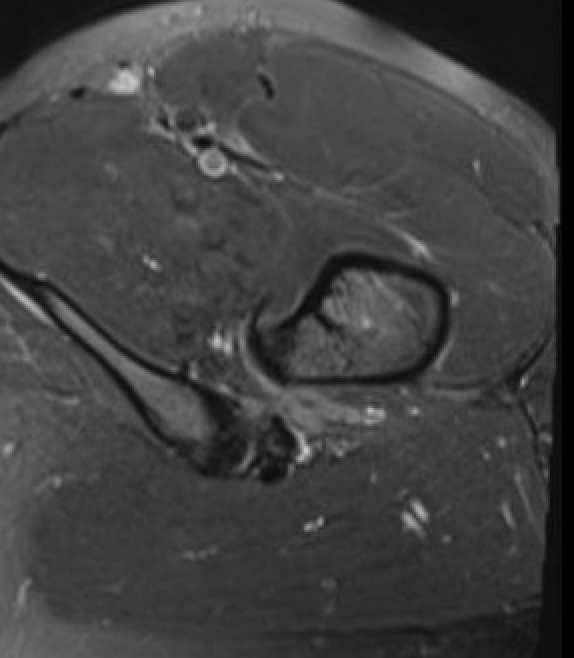

Posterior endoscopic technique

Approach

- make window in quadratus femoris

- medial circuflex flexoral artery superior

- first perforating branch of profunda femoris inferiorly

Advantage

- lesser trochanter is posterior

- preserves anterior insertion of iliopsoas tendon

Disadvantage

- risk of bleeding from medial circumflex / first perforating

- risk injury to sciatic nerve